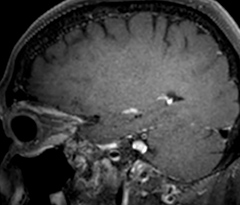

Giant cell arteritis

The 3D TSE T1w black blood MSDE sequence with fat suppression has an isotropic 0.8 mm voxel size and sagittal oblique and axial reformats are made. The images show superficial temporal artery thickening and peri-arterial fat infiltration. The 3D TSE PDw black blood MSDE with fat suppression has 0.55 mm isotropic voxels. The images shows focal involvement of the frontal branch of the superficial temporal artery.

3D TSE T1w BB MSDE

3D TSE PDw BB MSDE

So, what is the actual impact of having more information and more diagnostic confidence? According to Dr. Savatovsky, “One of the indications I’ve seen where using Elition is most impactful is in patients with suspected giant cell arteritis. As an ophthalmologic hospital, we see many patients with suspected giant cell arteritis. Usually we were performing MRI to help us rule out an ischemic stroke, and to verify that the supra aortic vessels are undamaged. With Elition, we still do this, but now we can add on more detailed high-resolution black-blood sequences on superficial arteries. This provides us with high confidence levels for diagnosis of giant cell arteritis (GCA) and as a result, some patients are not sent for a biopsy anymore. A patient who has a normal MRI will not require a biopsy and can be discharged from the hospital in the same day. Before, such a patient would have to stay for about a week, just to find that their biopsy results were negative. We have at least three or four patients a week with suspected giant cell arteritis. For a great deal of these patients we can have a direct impact on their hospital stay.”